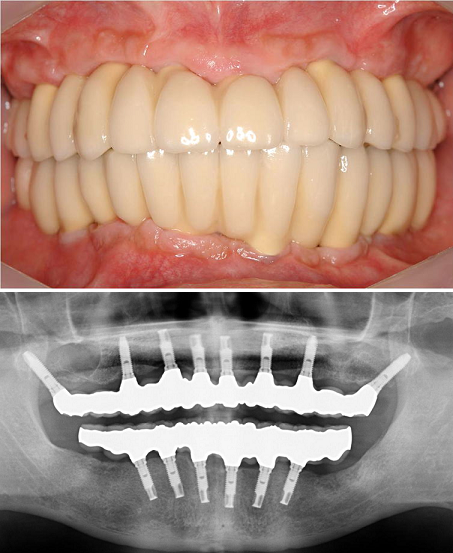

無歯顎(歯が全部ない状態で、上顎だけ、下顎だけ、あるいは上顎・下顎の両方)の患者さんでは、インプラントを埋め込んだ日に仮の歯を付けることができます。 この治療法は即時荷重(immediate loading)と呼ばれ、インプラント治療の中で最も高度な技術を要する治療であり、当院は1997年から行っている。。この成果は、ブローネマルクインプラントの発祥地であるスウェーデンのイエテボリで2000年7月に開催されたInternational TeamDay of Nobel Biocare(この会議には世界的な著名人をはじめ約2000名のインプラント関係者が世界中から参加されました)にて、招待講演(Immediate loading of Complete Arches Prostheses with Implant support from Posterior mandiblae and maxillae)として発表した。この内容はインプラント関係では最も権威のある International Journal of Oral and Maxillofacial Implants (JOMI) という学会雑誌に掲載された( Immediate Loading of Brånemark System Implants Following Placement in Edentulous Patients: A Clinical Report . 2000;15(6):824-830 )。

無歯顎即時荷重において “All-on-4” がトピックスとなっており、治療オプションの1つとして利用価値があるかもしれないが、十分な知識と術式の習得をした上でないとトラブルが生じる可能性が高い。また、①日本人の上顎では適用できない症例も多い、②補綴の自由度がない、③第2大臼歯間の咬合再建ができない、➃最遠心インプラントの角度付アバットメントにおけるアバットメントスクリューの緩みによるトラブル、➄長期のデータがない、などが問題点と考えられ、当院では応用していない。補綴の自由度に関しては、 インプラント4本での“All-on-4” は ワンピース(一続きの)の補綴物しか作製できないが、 8本ないしは10本のインプラントを埋入すれば、前歯部、両側臼歯部の 3つに分割した補綴物にすることが可能である。

無歯顎即時荷重において “All-on-4” がトピックスとなっており、治療オプションの1つとして利用価値があるかもしれないが、十分な知識と術式の習得をした上でないとトラブルが生じる可能性が高い。また、①日本人の上顎では適用できない症例も多い、②補綴の自由度がない、③第2大臼歯間の咬合再建ができない、➃最遠心インプラントの角度付アバットメントにおけるアバットメントスクリューの緩みによるトラブル、➄長期のデータがない、などが問題点と考えられ、当院では応用していない。補綴の自由度に関しては、 インプラント4本での“All-on-4” は ワンピース(一続きの)の補綴物しか作製できないが、 8本ないしは10本のインプラントを埋入すれば、前歯部、両側臼歯部の 3つに分割した補綴物にすることが可能である。

以上の観点から当院では、患者さんの信頼をなくさないための予知性が高い、そして機能的かつ審美的に優れた即時荷重を300例以上行い、良好な結果を得ている。

4年前からノーベル・バイオケア社のNobelGuideによるコンピュータ・ガイディッド・サージェリー(Computer-guided surgey: コンピュータにてインプラント治療計画を立て、その通りに手術が可能になる手術法)にて低侵襲でかつ短時間の治療が可能となった。

しかし、上顎では上顎洞(上顎骨にある空洞で副鼻腔の一つ)との関係で骨量が少ない症例が多く、グラフトレス(graftless: 骨造成をしないという意味)では対応できず、最低限度のグラフト(graft: 骨造成をするという意味)を行う必要があり、当院ではそれを行うことにより、上顎無歯顎症例の96%に即時荷重を可能にしている。

4年前からノーベル・バイオケア社のNobelGuideによるコンピュータ・ガイディッド・サージェリー(Computer-guided surgey: コンピュータにてインプラント治療計画を立て、その通りに手術が可能になる手術法)にて低侵襲でかつ短時間の治療が可能となった。

しかし、上顎では上顎洞(上顎骨にある空洞で副鼻腔の一つ)との関係で骨量が少ない症例が多く、グラフトレス(graftless: 骨造成をしないという意味)では対応できず、最低限度のグラフト(graft: 骨造成をするという意味)を行う必要があり、当院ではそれを行うことにより、上顎無歯顎症例の96%に即時荷重を可能にしている。

<グラフトレス症例>